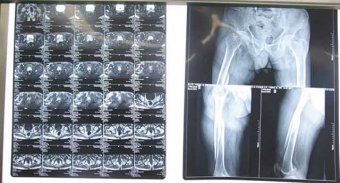

•   71歲患者左股骨頸骨折治愈 日期:2016-12-16 09:23:00 點(diǎn)擊:1658 好評:39

潘先生,男,71歲,五個(gè)月前騎自行車時(shí)不慎摔倒,傷及左髖部,傷后即感左臀部壓痛,左下肢短縮,活動(dòng)受阻。來到濰坊市市立醫(yī)院骨科門診。 脊椎微創(chuàng)科主任、副主任醫(yī)師孫守全為患者進(jìn)行...